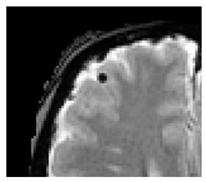

| Cerebral microbleeds: | Perivascular haemosiderin deposits that leak from capillaries, implying the breakdown of the blood–brain barrier and endothelial dysfunction [28] | ![]() | <10 mm Hypointense: T2*-GRE, SWI Isointense: DWI, FLAIR, T2, T1 |